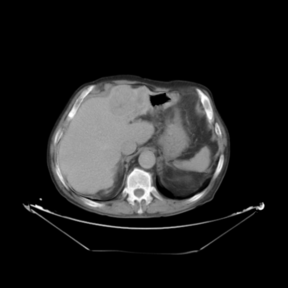

In addition to the previous measurements, the visual outcomes of two of the experiments are shown in Figures 3 and 4, whose purpose is to highlight the most illustrative differences (from a medical point of view) between the results provided by the compared methods. In Figure 3, we observe a normal size of the liver, with discretely irregular contours and homogeneous signal intensity. In hepatic segment II, there is a lesion of 40 mm of maximum axis, encapsulated and with well-defined contours and heterogeneous enhancement in arterial phase (after administration of intravenous contrast), suggestive of hepatocellular carcinoma (HCC). In this slice of the CT scan, we can also observe the aorta that shines in the arterial phase, the lower area of the stomach and the upper area of the spleen. In Figure 4, the liver has a normal size with discretely irregular contours in relation to changes due to chronic liver disease. In hepatic segment IV, a 36 mm diameter focal lesion is identified, which has arterial phase enhancement with a small area of necrosis of 13 mm; it corresponds to a HCC previously chemoembolized with partial necrosis. In this slice of CT, we can also observe the aorta, the gastric chamber and the spleen. When comparing the two methods under study, it can be seen how in Figure 3 the resulting registered datasets are very similar. However, looking closely, it can be noticed that in the right part of the image (left side of the patient) the shape and width of the structures corresponding to the stomach and the spleen in Figure 3(d) match better those in the reference dataset. Likewise, the part of the rib at the upper right of the image is more similar to the same region in the reference dataset by using the proposed method. Regarding the experiment shown in Figure 4, it can be easily appreciated how the geometrical matching (with respect to the reference dataset, Figure 4(a)) of the structures in the right side of the image (specially the gastric chamber) is visually more satisfactory in Figure 4(d). Moreover, the area of tumor necrosis which results from the proposed method is also slightly better aligned.

Arterial phase (reference dataset, R) Portal venous phase (template dataset, T)

(a) Arterial phase (reference dataset, Failed to parse (MathML with SVG or PNG fallback (recommended for modern browsers and accessibility tools): Invalid response ("Math extension cannot connect to Restbase.") from server "https://mathoid.scipedia.com/localhost/v1/":): {\textstyle R}

)

(b) Portal venous phase (template dataset, Failed to parse (MathML with SVG or PNG fallback (recommended for modern browsers and accessibility tools): Invalid response ("Math extension cannot connect to Restbase.") from server "https://mathoid.scipedia.com/localhost/v1/":): {\textstyle T}

Registered template, T_u (CR-based method) Registered template, T_u (proposed method)

(c) Registered template, Failed to parse (MathML with SVG or PNG fallback (recommended for modern browsers and accessibility tools): Invalid response ("Math extension cannot connect to Restbase.") from server "https://mathoid.scipedia.com/localhost/v1/":): {\textstyle T_\mathbf{u}}

(CR-based method)

(d) Registered template, Failed to parse (MathML with SVG or PNG fallback (recommended for modern browsers and accessibility tools): Invalid response ("Math extension cannot connect to Restbase.") from server "https://mathoid.scipedia.com/localhost/v1/":): {\textstyle T_\mathbf{u}}

(proposed method)

Figure 4. Visual outcomes of experiment 5 (slice 12): registration of arterial and portal venous phases of patient 2